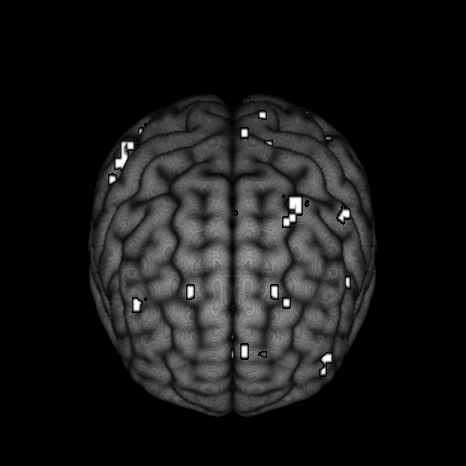

Our motivating example comes from a single subject in a fMRI experiment examining a face-repetition stimulus. The experiment involves the presentation of either famous faces (F) or non-famous faces (N) with each type of face presented two times. Convolving this experiment design with the canonical hemodynamic response function and its time and dispersion derivatives leads to a design matrix with twelve columns plus one extra column for an intercept term in the regression model. After performing the necessary pre-processing steps as described in Penny et al. (2005), we fit a simple linear regression at each of the voxels. After obtaining the residuals from each voxel-specific fit, we fit an AR process up to order for each voxel using the “ar” function in R. We then selected the optimal AR orders based on the AIC criterion. Figure 1 displays a pictoral representation of the results.

Figure 1 shows considerable variablity in the estimated AR order across voxels. While most of the estimated optimal AR orders are 4 or less, higher orders up to are selected at some of the voxels. Furthermore, these estimated AR orders tend to show some extent of spatial clustering. If, as is often done, we simply model the data using a homogeneous low-order AR process, then the voxels with higher order estimated AR orders would be incorrectly modeled, and this inaccuracy in the modeling of temporal noise will have an impact on the inference on the covariates of interest (via underestimated standard errors), resulting in potentially false inferences about brain activation. To address this issue, we propose a spatially varying autoregressive order (SVARO) model, where the AR orders vary spatially across the brain. This is made possible by adopting a spike-and-slab prior with a stochastic search variable selection scheme. Spatial clustering of AR orders is incorporated by imposing an Ising prior (Ising, 1925) as the latent indicator for the spike and slab prior. We update the latent indicators using the Swendsen-Wang algorithm (Swendsen and Wang, 1987) alternating with Gibbs sampling in our MCMC algorithm. To prevent the phase transition problem associated with the Ising model, we derive theoretical bounds as in Li et al. (2015) and use these bounds to prevent critical slowing of the algorithm. We compare our model with the GLM-AR model of Penny et al. (2007) (implemented under two schemes: our self written MCMC sampler and the VB algorithm available in the SPM software) in terms of mean squared error (MSE) and sensitivity. We conduct these comparisons using two simulation studies and then compare results on the motivating data set.